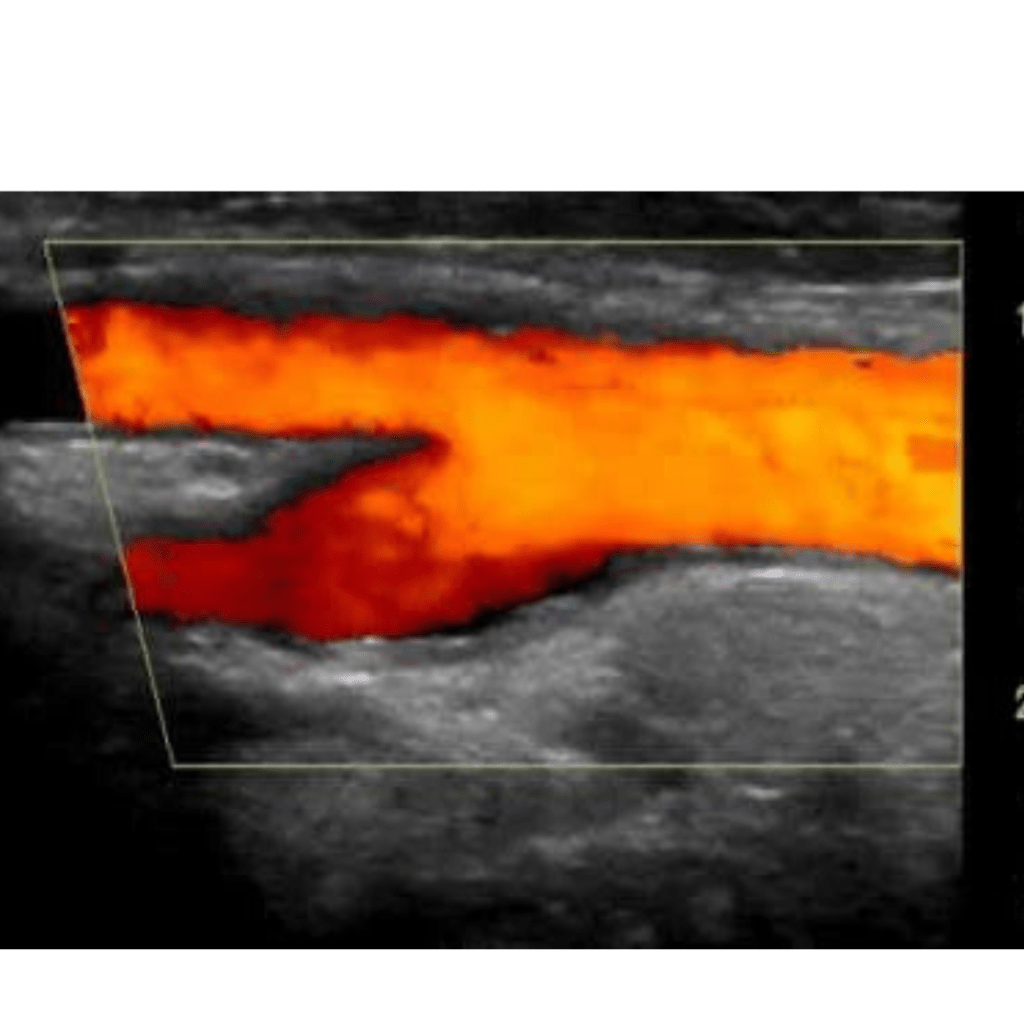

Vascular ultrasound is a non-invasive imaging test that uses high-frequency sound waves to evaluate the body’s circulatory system, specifically the arteries and veins. This procedure helps identify blockages, blood clots, and other vascular conditions.

Diagnosing Vascular Conditions: Vascular ultrasounds are essential for detecting issues such as blood clots, narrowed blood vessels, and other abnormalities in the circulatory system.

Evaluating Blood Flow: The test assesses how blood flows through your arteries and veins, aiding in the diagnosis of conditions like peripheral artery disease and venous insufficiency.